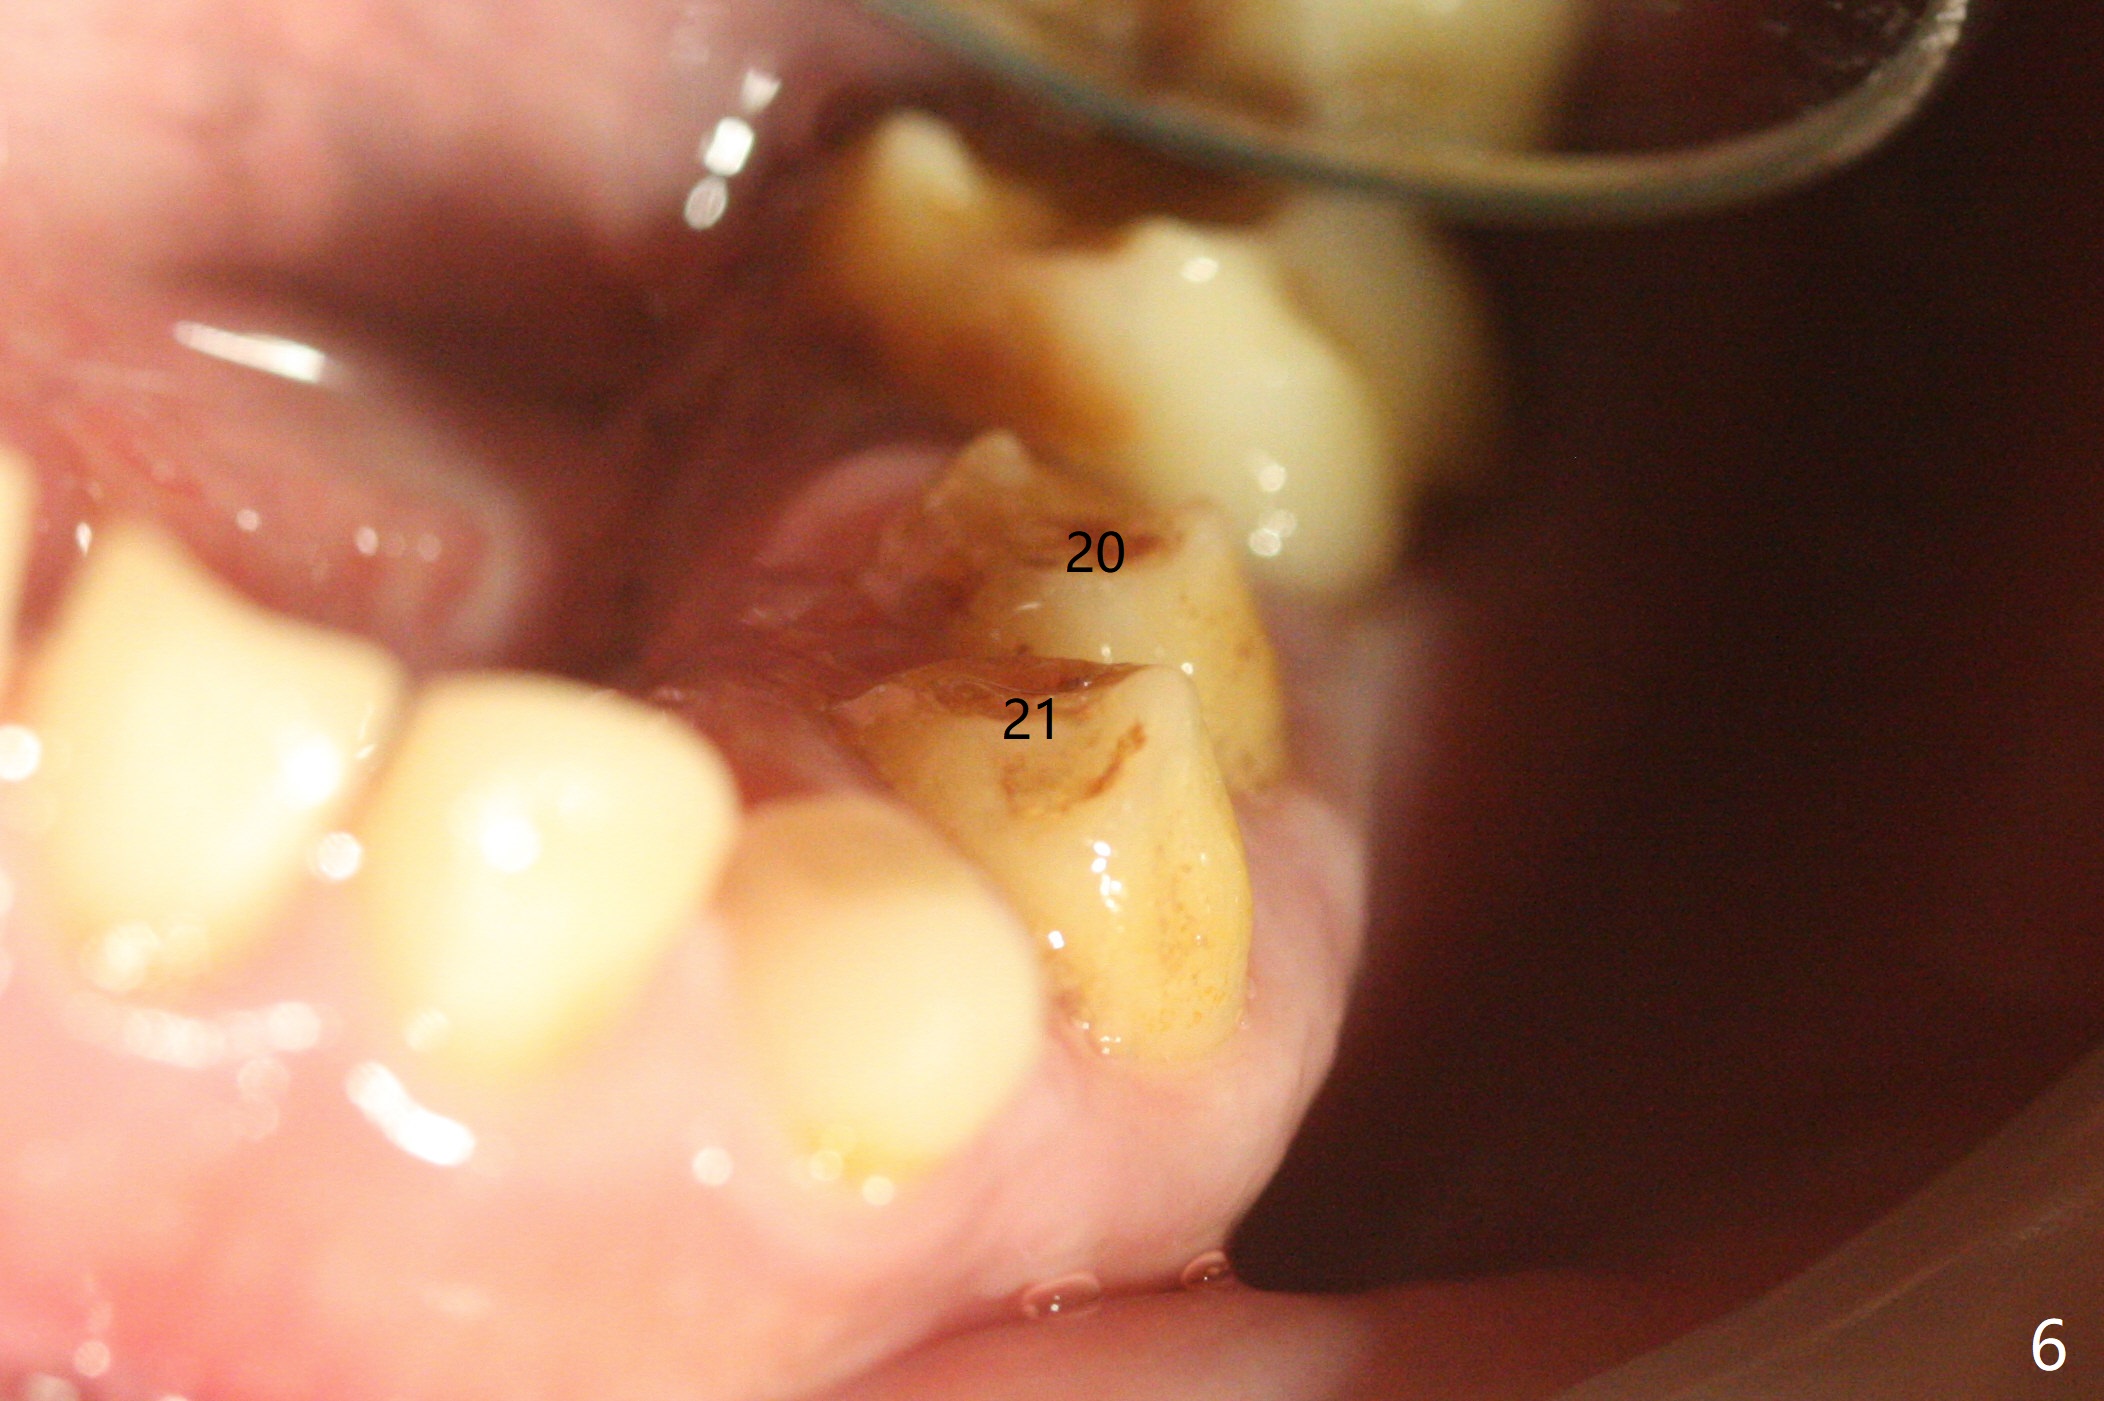

13岁男孩,每颗乳恒牙交换时乳牙都需要拔除,萌出的恒牙个子小,侧切牙反合(图二,五),对冷热敏感,不爱刷牙,口腔卫生欠佳(图三:13(结石)),父母要求诊治。今天在局麻下,左上洁治,没有局麻区域无法洁治,敏感,并且拔除H-J。S下沉,5,28埋伏(图七),其余乳磨牙都有龋齿。如何治疗?是釉质发育不全?暴露5,28前将拍摄CT。